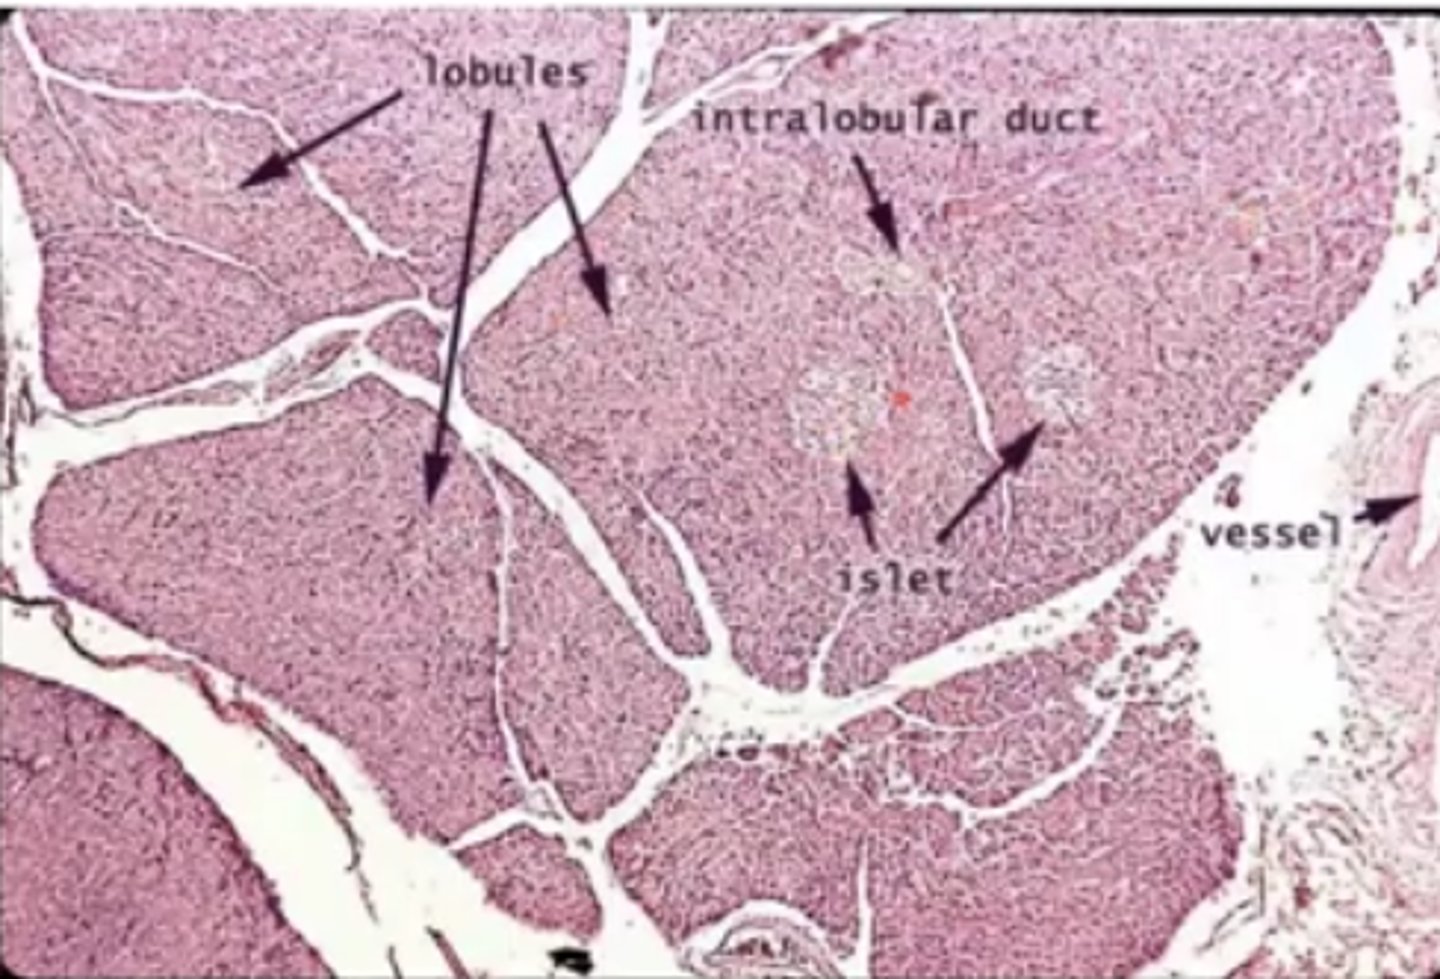

Pancreas

what is this?

insulin

What hormones does the pancreas produce?

Islets of Langerhans

what is this pointing to?

pancreas

what organ is islet of langerhans on